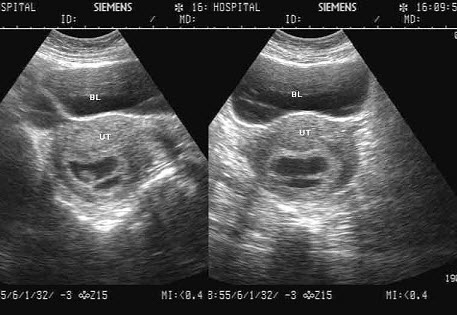

37、单项选择题

女,23岁,停经45天,阴道无异常分泌物,子宫附件声像图如下,图中所示为()

A.正常早孕孕囊及胚外体腔

B.双胎妊娠双孕囊

C.难免流产

D.子宫肌瘤

E.早孕并宫腔积液